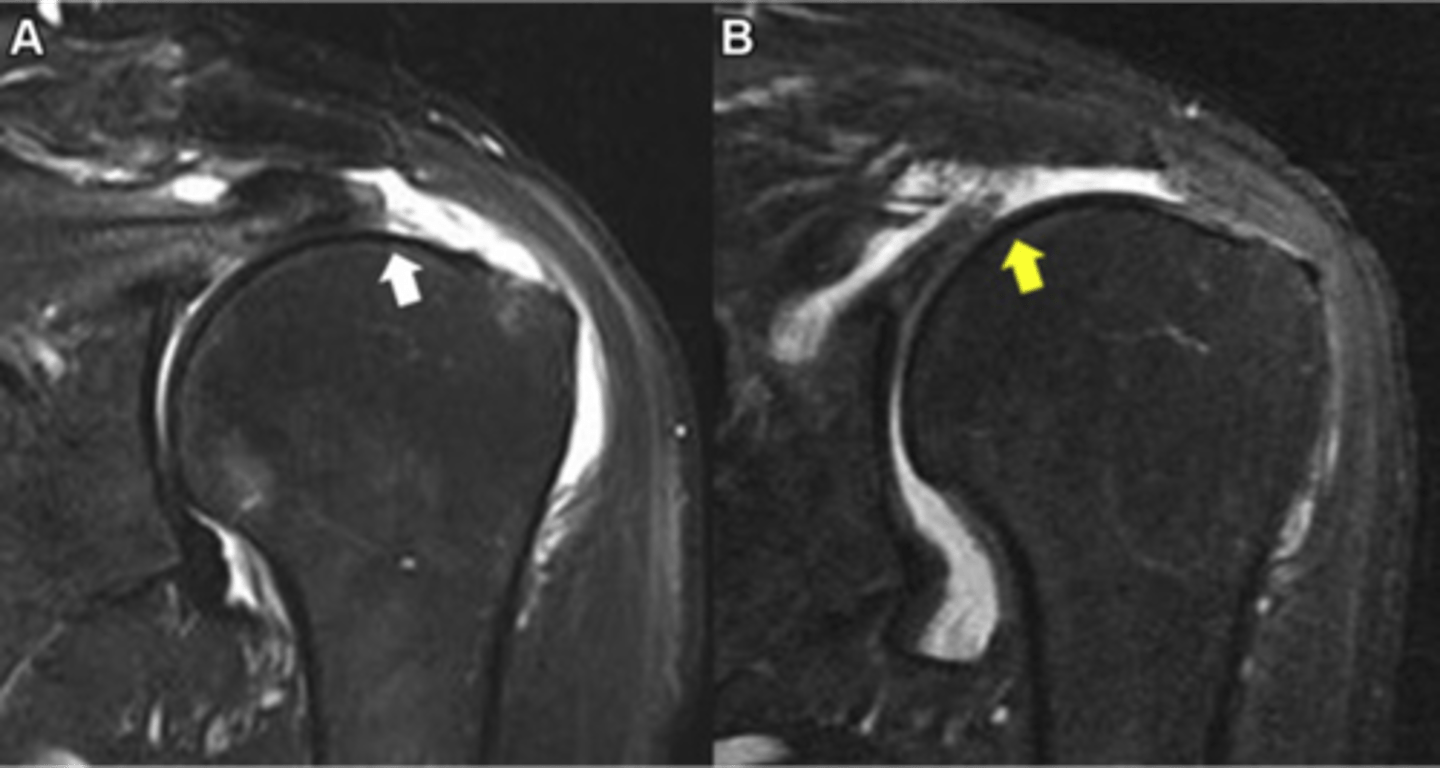

Complete thickness tear of the supraspinatus w/ major bucking and retraction as the muscle pulls the tendon back

What are these images depicting w/ the rotator cuff?

Supraspinatus tendon

What is this image calling out in white on the left and with a star on the right?